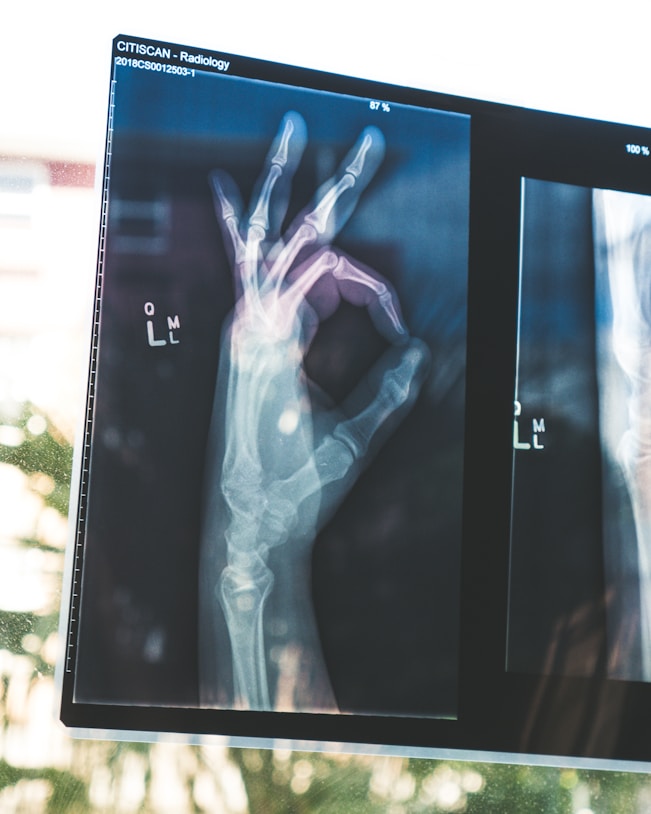

Bol koji se često percipira kao isključivo bol u kostima može biti kompleksan i zahteva pažljiv pristup. Prvo i najvažnije, pravilna dijagnoza predstavlja ključni korak ka razumevanju uzroka bola. Fizikalna medicina igra značajnu ulogu u proceni stanja, što obuhvata različite testove i slike kako bi se utvrdilo poreklo bola. U mnogim slučajevima, bol koji pacijenti doživljavaju može biti povezan s okolnim mekim tkivima, zglobovima ili čak i nervima, stoga je važno ne prevrednovati simptomatologiju.